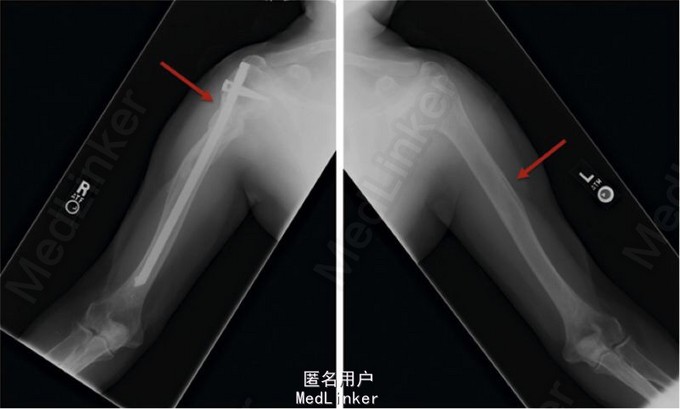

患者,男,65岁 患者因腰椎及股骨骨量减少,伴双侧肱骨多发非创伤性骨折(图1)就诊。